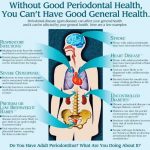

پریودنتیکس یا لثه درمانی چیست؟

پریودنتیکس (Periodontics ) شاخهای از دندانپزشکی است که بر پیشگیری، تشخیص و درمان بیماریها و شرایطی که بر ساختارهای نگهدارنده دندانها، بهویژه لثه و بافتهای اطراف آن تأثیر میگذارند، تمرکز دارد. واژه پریودنتیک از دو واژه یونانی «peri» به معنای اطراف و «odont» به معنای دندان گرفته شده است. بنابراین پریودنتیکس یعنی مراقبت از بافت های اطراف دندان که مسئول نگهداری از آن هستند.

به چه دندانپزشکی پریودنتیست گفته می شود؟

پریودنتیست (periodontist ) دندانپزشکی است موفق به دریافت مدت پریودنتولوژی شده و در پیشگیری، تشخیص و درمان بیماری های پریودنتال تخصص دارد. این متخصصان در درمان بیماری هایی مانند بیماری لثه، تحلیل رفتن لثه و آبسه های پریودنتال متخصص هستند. پریودنتیست ها از نزدیک با دندانپزشکان عمومی و سایر متخصصان دندانپزشکی برای ارائه مراقبت های بهداشتی جامع دهان و دندان همکاری می کنند.